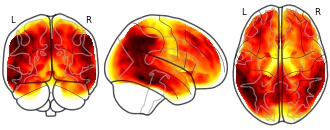

License information was derived automaticallyDescriptionMean gray matter hypometabolism in UCSF cohort (W-score). Gray-matter masked.

Higher W values indicate lower FDG-SUVR values in patients compared to controls.Collection description

Data from Strom et al, MedRxiv (2020), Brain (2021).

Summary mean images of FDG-PET, tau-PET, amyloid-PET, and MRI volume for UCSF and ADNI cohorts.Subject species